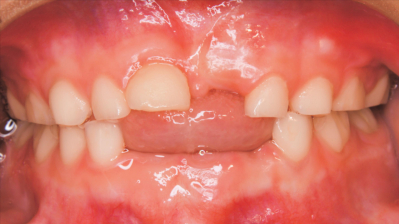

5歳の男児。口腔内診査を希望して来院した。6か月前に下顎両側乳中切歯が自然脱落し、2か月前に上顎左側乳中切歯と下顎左側乳側切歯が自然脱落したという。上顎右側乳中切歯の唇側傾斜がみられる。咬合時の口腔内写真を別に示す。

永久歯列において予想される咬合異常はどれか。1つ選べ。